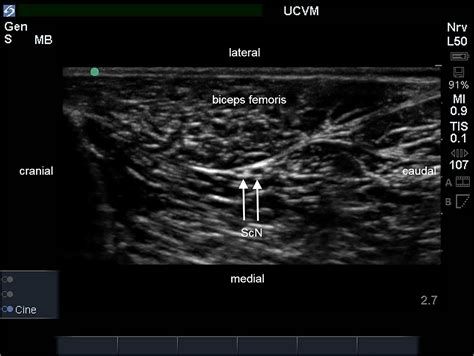

The success of the procedure relies heavily on precise placement. To ensure accuracy, modern medical practices utilize ultrasound guidance or nerve stimulation to visualize the nerve anatomy in real-time. This reduces the risk of nerve injury and ensures the medication is delivered precisely where it is needed.

Guidance Ultrasound or nerve stimulator identifies the precise location of the sciatic nerve.